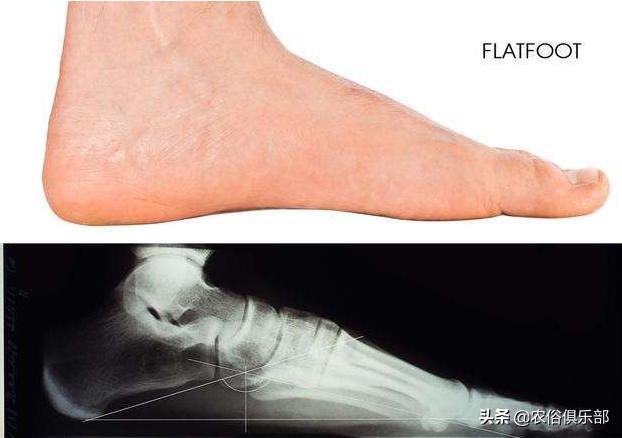

其实就是扁平足,老百姓们也叫它“平板脚”。

这个说法就很好理解了,平板脚其实就是脚中间没有弧度,整个脚就像平板一样,平坦坦的,能够完全接触到地面。

这样的脚有个问题,就是跑不快也走不久,很容易感到疲惫,行动不是很方便,也很容易引发一些脚部疾病。

平板脚其实也叫扁平足,专业来说就是,足弓低平或消失,拥有这种脚的人站立、行走的时候足弓塌陷,会引起足部疼痛。

这其实就是脚部的一种畸形,踝关节前内侧疼痛,长时间站立或步行是很难坚持的,甚至还会引发腰背痛等症状,严重的将无法正常行走和站立。

这种脚型有的是遗传,有的是后天的,比如脚长期负重站立,过度疲劳引发的,有的也是缺乏锻炼导致肌肉萎缩引发的,此外,穿鞋不当,鞋跟太高也会破坏人的脚型,成为平板脚!

不过除了遗传的平板脚,这种脚型其实是可以通过适当的运动恢复过来的。

不过平足并不一定就是平足症,只有那种平足者合并会疼痛的时候才需要治疗。

目前根据调查,在成人平足中,50岁以上的女性比较多,这其实也和女性穿高跟鞋的习惯有关,男性很少出现,除了遗传的外。

其实平足只要不是特别严重的,也不是什么大的毛病,并不需要太担心。